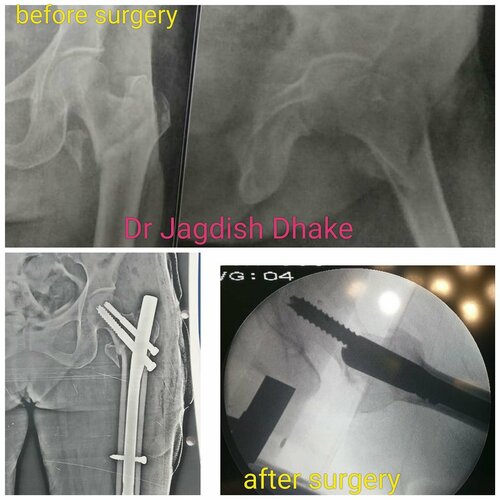

Case of fracture in thigh bone with multiple pieces of femur bone | Dr. Jagdish Dhake

19-year-old boy, hit by a speeding truck, had badly fracture in thigh bone with multiple pieces of femur bone. Patient shifted from Ahmednagar ...